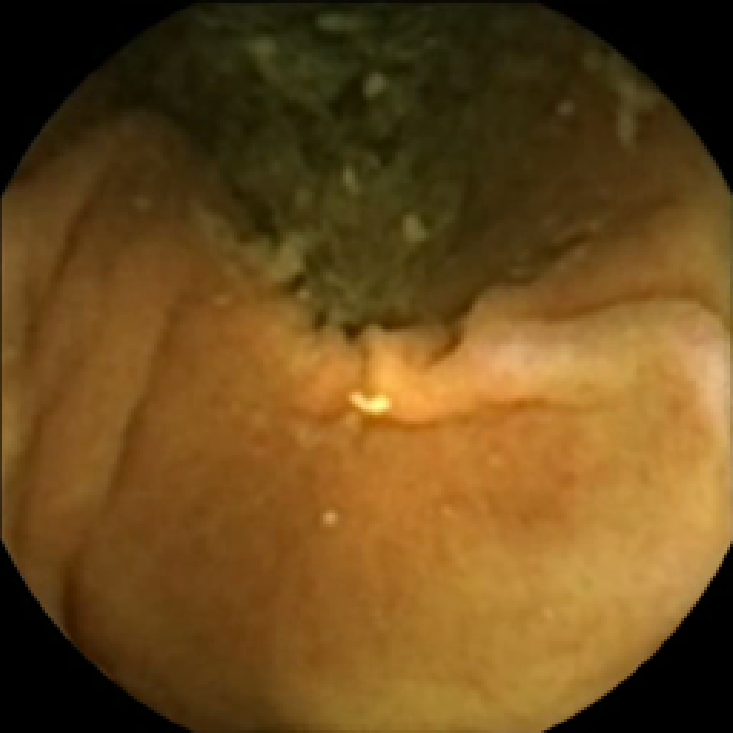

In Figure 5 we show the circles of radius corresponding to the features that were correctly classified as polyps by (29). We observe that the classifier was able to identify the polyps of a variety of shapes even in the presence of small amounts of trash liquid (first row) or when the polyps are located next to mucosal folds (rows two to four in column (c)).

The examples of incorrect classification of frames are presented in Figure 6. The first two examples show false negatives, each highlighting a possible source of classification error. The example in column (a) shows the case where the feature corresponding to the polyp was too stretched out and thus was rejected by the eccentricity criterion (21). In contrast, the feature corresponding to the polyp in column (b) has passed the combined geometric criterion (22), but the radius was below the threshold of the binary classifier. Examples in columns (c) and (d) show the two sources of possible false positives. The false positive detection in column (c) is due to insufficient illumination correction. The bright spot is not fully corrected at the pre-processing stage and subsequently generates a polyp-like feature in the mid-pass filtered frame that happens to pass through all the criteria. Finally, in column (d) a mucosal fold is classified as polyp. Note that such cases are the most difficult to deal with, as the mucosal folds can often be hard to distinguish from polyps even for a human operator.